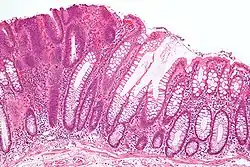

Micrograph of a tubular adenoma (left of image), a type of colonic polyp and a precursor of colorectal cancer. Normal colorectal mucosa is seen on the right of the image. H&E stain.

Adenoma is a benign tumor of glandular tissue, such as the mucosa of stomach, small intestine, and colon, in which tumor cells form glands or gland-like structures. In hollow organs (digestive tract), the adenoma grows into the lumen - adenomatous polyp or polypoid adenoma. Adenomatous polyps may be classified based on morphology in order to identify lesions at increased risk of malignant transformation. For example, adenomatous polyps in the colon may be pedunculated (lobular head with a long slender stalk) or sessile (broad base).

The adenomatous proliferation is characterized by different degrees of cell dysplasia (atypia or loss of normal differentiation of epithelium) irregular cells with hyperchromatic nuclei, stratified or pseudostratified nuclei, nucleolus, decreased mucosecretion, and mitosis. The architecture may be tubular, villous, or tubulo-villous. Basement membrane and muscularis mucosae are intact.